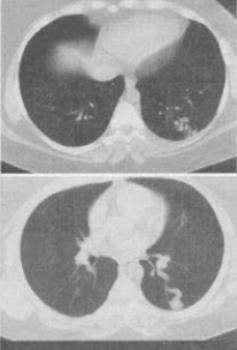

患者男,30岁,偶尔干咳,结合图像,最可能的诊断是()。

A、左下肺感染

B、左下肺结核

C、左下肺错构瘤

D、左下肺炎性假瘤

E、左下肺AVM

正确答案:

E